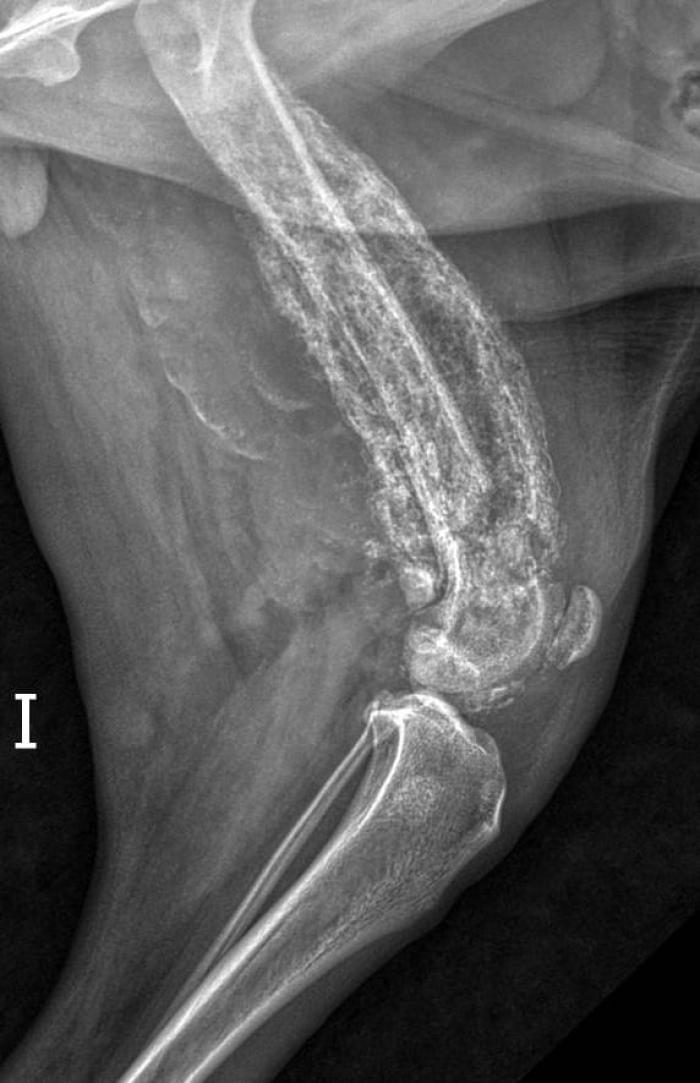

Se realizó un examen radiológico de las extremidades afectadas, en el cual se detectaron lesiones osteolíticas junto con periostitis (Figura 1).